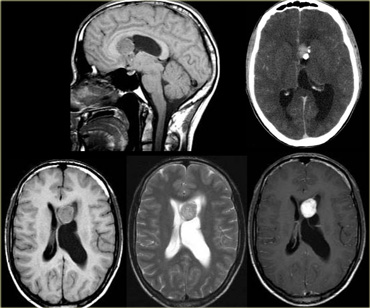

Low on T2

Most tumors will be bright on T2WI due to a high water content.

When tumors have a low water content they are very dense and hypercellular and the cells have a high nuclear-cytoplasmasmic ratio.

These tumors will be dark on T2WI.

The classic examples are CNS lymphoma and PNET (also hyperdense on CT).

On the left some examples of tumors with a low signal intensity on T2WI.

1. Melanoma metastases have a low SI on T2WI as a result of the melanin.

2. GBM can have a low SI on T2WI because sometimes they have a high nuclear-cytoplasmic ratio. Most GBM's, however, are hyperintense on T2WI.

3. PNET typically has a high nuclear-cytoplasmic ratio. PNET is mostly located in the region of the 4th ventricle, but another, less common, location is in the region of the pineal gland.

4. Mucinous metastases can have a low SI on T2WI because they often contain calcifications..

5. Meningiomas are mostly of intermediate signal.

They can have a high SI on T2WI if they contain a lot of water.

They can have a low SI on T2WI if they are very dense and hypercellular or when they contain calcifications.